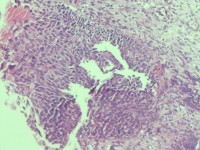

宫颈活检组织

性别

女

年龄

43岁

临床诊断

宫颈病变

一般病史

宫颈癌筛查:hpv16(+))

标本名称

宫颈组织

大体所见

灰白色组织

老师们看看,高级别累腺吗